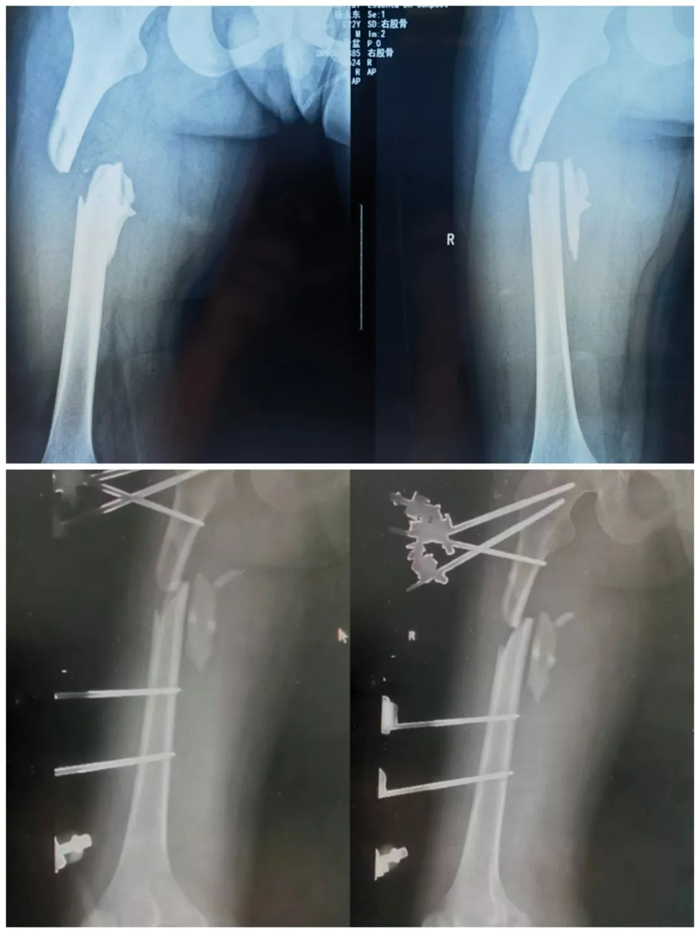

近日,一名22歲青年男性騎車不慎摔倒,右下肢損傷嚴重,被緊急送至我院。急診檢查發現患者右大腿明顯腫脹畸形,右側膝踝和足部活動受限,右下肢感覺麻木,血運極差。初步診斷股骨干骨折合并右下肢神經血管損傷。

創傷一科副主任楊錫明接到急診電話后,立即組織醫護團隊準備搶救,開通綠色通道并聯系血管外科急會診,給予患者完善術前相關檢查、備血、補充血容量并立即將患者送往手術室。經探查發現患者腘窩處肌肉、筋膜、韌帶斷裂,股動脈遠端及腘動脈無搏動、管壁無彈性,挫傷嚴重。血管外科主任徐存東組織科室人員立即行腘動脈切開探查,發現腘動脈內有血栓,行取栓后血運不佳,考慮動脈損傷嚴重,當機立斷決定取同側大隱靜脈行血管移植。血管外科副主任李強沉著應對,“取長補短”,使用血管縫合線將患者自體靜脈移植到動脈端。與此同時,創傷一科副主任劉志率領團隊對患者一期實施股骨骨折閉合復位+右膝外固定架固定術。

經過3個多小時的連續奮戰,順利完成了腘動脈自體靜脈搭橋移植術+患肢外固定支架固定術。患者右下肢血供終于恢復,手術順利結束。術后又經過ICU、普通病房的精心治療護理,目前患者肢體恢復良好,無明顯并發癥,已康復出院。